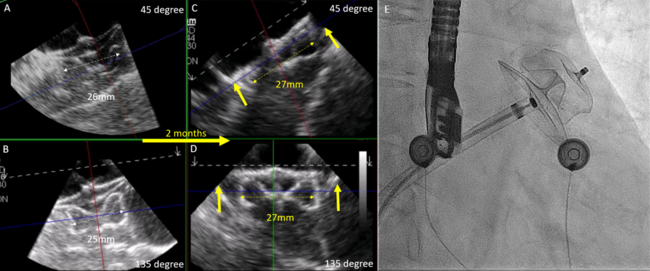

The patient presented is a 73-year-old woman with a 6-month history of persistent AF and a CHA2DS2-VASc score of 4. Pulmonary vein antral isolation (PVAI) was first achieved using the 31-mm FARAPULSE PFA catheter (Boston Scientific). Significant pulmonary ridge edema was observed immediately after ablation (Figure 1A and B). The diameter of the LAA landing zone was 24 x 21 mm on the 3-dimensional trans-esophageal echocardiography (TEE), measured at a mean left atrial pressure of 14 mm Hg. A 28-mm Amplatzer Amulet device (Abbott) was deployed at an optimal position in the LAA under TEE and fluoroscopy guidance (Video 1). The device was stable on a tug test with satisfactory compression and no residual flow (Figure 2A, B, and E; Video 2). However, follow-up TEE performed 2 months after the procedure showed proximal migration of the LAAO device (Figure 2C and D, Video 3) with resolution of pulmonary ridge edema (Figure 1C). Another TEE repeated 1 month later showed a stable device position. In view of the device migration with a potential sealing issue and uncertain device endothelialization, the patient was advised to continue oral anticoagulant therapy for stroke prophylaxis.